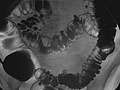

• In a single-contrast study, the colon is filled with barium. This outlines the intestine and shows large abnormalities.

• In a double-contrast or air-contrast study, the colon is first filled with barium, and then the barium is drained out. This leaves only a thin layer of barium on the wall of the colon. The colon is then filled with air. This provides a detailed view of the inner surface of the colon. It makes it easier to see narrowed areas (strictures), diverticula, and swelling.

Barium enema

Normal:

The colon looks normal.

Abnormal:

One or more problems in the colon are found, such as:

• A section of colon that did not fill with barium.

• A narrowing (stricture) in the bowel.

• Polyps or growths on the inner wall of the colon.

• Sacs in the colon wall (diverticulosis).

• Problems with defects and swelling (colitis) of the lining of the colon.

• A narrowed segment or a twisted loop of bowel, causing an obstruction.

• Telescoped bowel in a child, which is a sign of intussusception. The barium enema may be used as a treatment to return the bowel to its normal position.